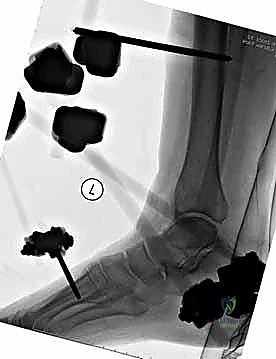

هنا تبرز براعة هذا الإجراء. يتم إدخال دبابيس معدنية (Pins) في العظم السليم فوق وتحت منطقة الكسر، ثم تُوصل هذه الدبابيس بإطار معدني خارجي (Frame) خارج الجلد.

3. إدخال الدبابيس (Pin Placement)

باستخدام جهاز الأشعة السينية المتحرك داخل غرفة العمليات (C-arm)، يقوم الدكتور هطيف بتحديد الأماكن الآمنة (Safe Corridors) لإدخال الدبابيس المعدنية (Schanz pins). هذه الأماكن يتم اختيارها بدقة متناهية لتجنب إصابة الأعصاب أو الأوعية الدموية الحيوية في الساق. يتم عمل شقوق صغيرة جداً في الجلد وإدخال الدبابيس في العظم السليم فوق وتحت الكسر.

5. تركيب الإطار الخارجي (Frame Assembly)

بمجرد أن تصبح العظام في الوضع الصحيح، يتم توصيل الدبابيس البارزة من الجلد بقضبان معدنية (Rods) أو إطار دائري باستخدام مشابك (Clamps) خاصة. يتم إحكام ربط هذه المشابك لتثبيت العظام بقوة ومنعها من الحركة تماماً.